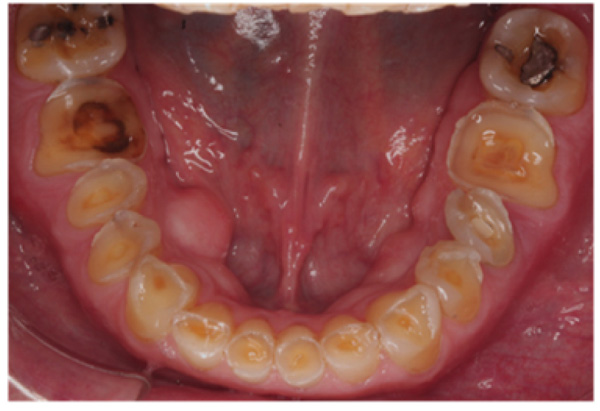

The patient presented with competent lips, an average lip line, normal TMJ function, and a mild Class II Division I incisor relationship with an increased overbite. The preoperative pan-oral radiograph is shown in Fig. (1). Boney exostoses and a large mandibular torus in the lower right mandible were present. The intra-oral presentation of the teeth is shown in Figs. (2-6). The patient had good oral hygiene and a healthy periodontium. The teeth had a glossy, smooth, and glazed appearance, showing cupping of the occlusal surfaces with significant loss of hard tissue and yellow color from the underlying dentine. This presentation was indicative of severe generalized tooth wear with exposed dentine in all sextants. The palatal, occlusal, and incisal surfaces were mainly affected, with lower buccal surfaces exhibiting more wear than the lower lingual, resulting in a reverse curve of Monson. The maximum BEWE score of 18 was recorded, meaning that the tooth with the most severe wear in each sextant had greater than 50% surface loss [9]. Several posterior teeth had amalgam restorations with defective margins (FDI 16, 26, 27, 37, and 47), as shown in Figs. (5 and 6). All teeth responded normally to pulp sensibility tests (cold test). The radiographs did not show any apical pathology to be present, but the pan-oral shows the scooped-out appearance of the lower molars.